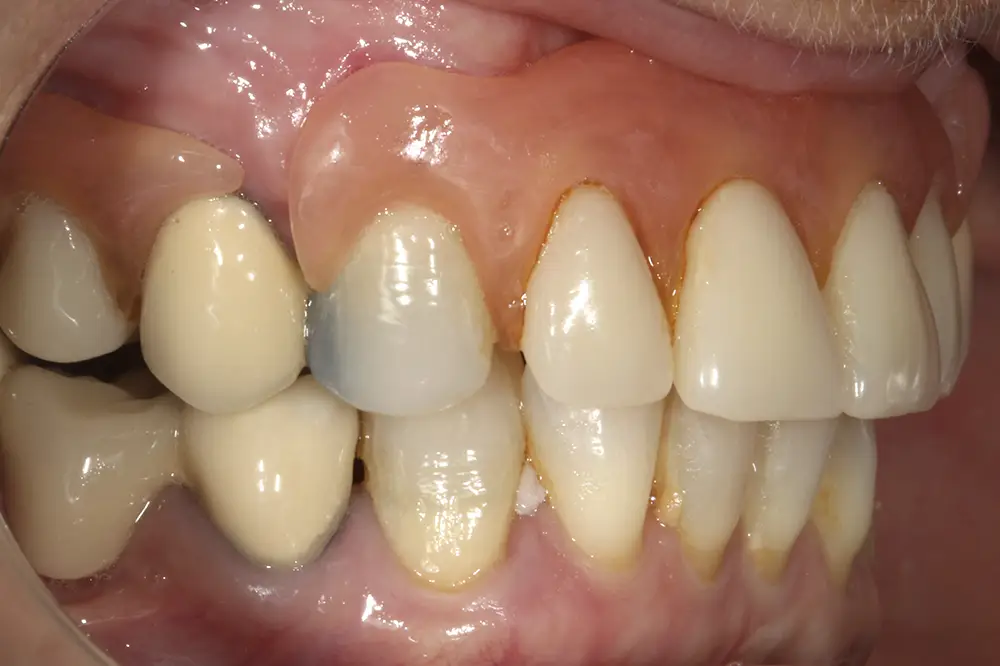

Al retirar las prótesis en las imágenes laterales, observamos además un colapso de la zona anterior y recesiones en todas las piezas que aún conserva la paciente (figs. 5 y 6). En la radiografía inicial observamos pérdidas óseas elevadas en el molar del primer cuadrante y el premolar de este mismo sector, por lo que se decide su exodoncia y regeneración con PRGF, que se realizará el mismo día de la primera fase de inserción de los implantes. En el arco inferior hay también problemas con los sectores posteriores, con pérdidas óseas en el cuarto cuadrante y signos de fractura vertical en el puente 44-46 y caries radicular en las piezas 35 y 36 (fig. 7). Por ello, estas piezas inferiores son también candidatas a la exodoncia, regeneración y reposición con implantes dentales, para lograr una posterior rehabilitación funcional.

Figs. 5 y 6. Imágenes laterales de la paciente sin su prótesis. Al retirarla, se hace evidente el colapso de la dimensión vertical y la pérdida ósea y recesión de los dientes pilares que sostienen la prótesis removible.